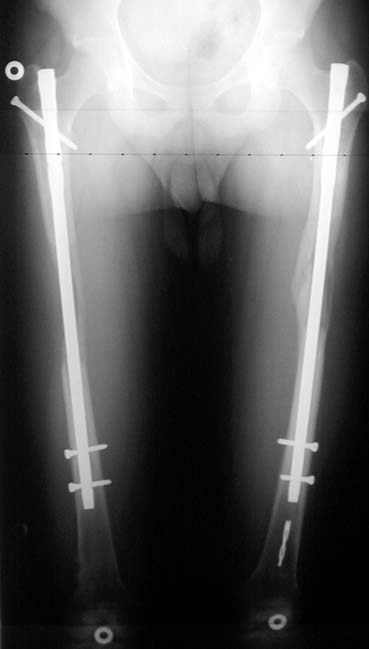

Biz son zamanlarda, seçilmiş vakalarda, uzatma sonrası uzunluğu ve “alignment’ı” korumak amacı ile unilateral dinamik aksiyel fiksatör ve kilitli intramedüller çivi kombinasyonunu tercih etmekteyiz. Bu yöntemin ön şartları medullanın en dar çapının 7 mm.’den geniş olması ve uzatma sonrası distalde en az 8 cm. uzunluğunda çivi kalabilmesidir. İntramedüller çivi hem uzatma esnasında femurun üzerine gelen makaslama ve bükülme kuvvetlerini nötralize etmekte hem eksternal fiksasyon süresini kısaltmakta, hem de yeni oluşan kemiği kırıklara karşı korumaktadır. Serimizde bir vakada subtrokanterik femoral osteotomi yapılmıştır. İntramedüller çiviye rağmen varus angulasyonu oluşması yönünde bir dezavantaj tespit etmedik.

Örnek sayılarının az olmasına rağmen etyolojik faktör, yaş, patolojinin yerleşim yeri, miktarı gibi faktörler yönünden benzer iki grubu karşılaştırmayı amaçladık. Eşlik eden tibial uzatma, osteotomi yeri gibi ayrıntıları bu ilk çalışmada göz ardı ettik. Prospektif randomize karşılaştırmalı bioistatistik analiz yapmamız için örnek sayımız azdır. Bu çalışmanın sonuçları matematiksel olarak anlamlı istatistik veriler içermese de belirli bir tecrübenin aktarılması yönünde ülkemizdeki ilk ve tek örnek olduğuna inanıyoruz.

İntramedüller çivi ve eksternal dinamik aksiyel fiksatör kombinasyonu teknik olarak standart İlizarov uygulamalarından daha zordur. Ancak şu avantajlar yöntemi cazip hale getirmektedir; eksternal fiksasyon süresinde kısalma, refraktüre karşı korunma, erken rehabilitasyon, azami hareket genişliği kazanma ve günlük yaşam konforu. Bu avantajlar artan maliyet , artan kan kaybı ve potansiyel derin infeksiyon gibi dezavantajların önüne geçmektedir. Sonuç olarak, bulgularımızın eşliğinde, intramedüller çivi üzerinden femoral uzatma tekniğinin güvenilir ve dayanıklı bir metod olduğunu ve bizce standart İlizarov uygulamalarına üstünlük sağlayan avantajlar getirdiğini söyleyebiliriz.